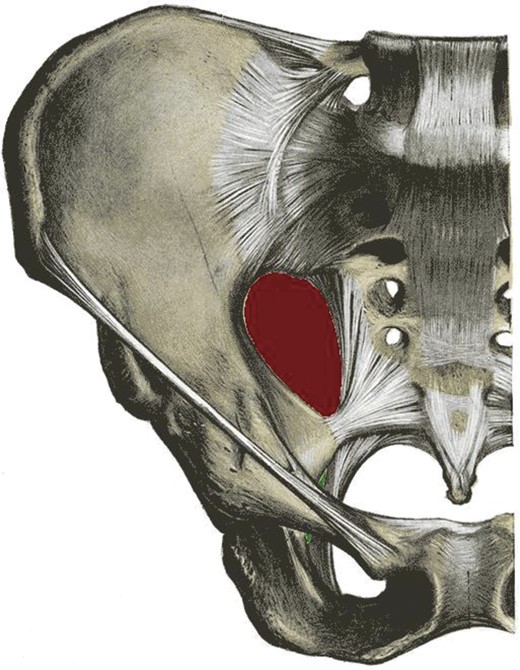

Sciatic hernias are one of the rarest types of hernia and often pose diagnostic difficulty to the clinician [1]. A sciatic hernia is defined as herniation of intraperitoneal contents through either the greater or lesser sciatic foraminae (Fig. 3). The majority of sciatic hernias are found in women (77%) with more than one-third of these being aged 60 or over [1]. The contents are variable and hernias containing ovaries, ureters, bladder, small and large intestine, omentum and dermoid cysts have been reported [1–6]. The wide variability in contents leads in turn to a range of presentations. Cases have been reported with both acute and chronic symptom duration [2–5]. Half of patients report non-specific abdominal or pelvic pain and one third have a mass on clinical examination [1]. Sciatica, intestinal obstruction, urinary sepsis and hydronephrosis have also been described [1–5]. Diagnostic laparoscopy or laparotomy is often required to fully evaluate the sac contents and to repair the defect [2, 3, 5]. In symptomatic patients, surgical repair is indicated due to the high risk of bowel strangulation [1, 3].

Pelvis demonstrating the greater (red) and lesser (green) sciatic foraminae.